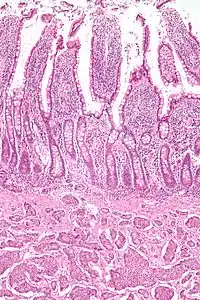

| Micrograph of a neuroendocrine tumor. H&E stain. | |